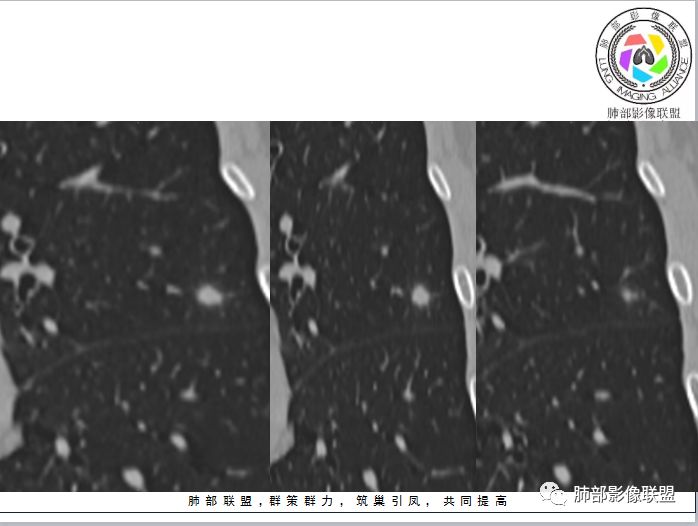

水晶石头:

患者中年男性,体检发现。查肿瘤标志物、结核菌素实验、肝肾功能无明显异常。胸部CT:左肺上叶胸膜下类圆形实性结节,可见分叶、平直及血管贴边征象,周围可见磨玻璃影。综合考虑良性病变,隐球菌可能大,鉴别腺癌。

中年男性,平素体健,无呼吸异常主诉及体征,查血无明显异常。体检发现左肺上叶实性类圆形结节影,部分层面周围有磨玻璃晕症,可见血管进入,考虑良性,考虑炎性肉芽肿,考虑隐球菌感染可能,需与腺Ca、PSP鉴别

左上肺结节,边缘有晕,部分边缘清,部分模糊,无收缩力,贴血管边缘平直,考虑隐球菌可能 ,鉴别粘液腺癌。

左肺上叶结节,边缘光滑清晰,部分边缘平直,周围有晕,血管贴边,考虑炎性肉芽肿,隐球菌。鉴别浸润腺癌。

左肺上叶结节,轻度分叶,滋养血管征,晕中软毛刺,边缘偏模糊,考虑隐球菌,鉴别诊断黏液腺癌,晕偏一侧边缘偏清楚。

中年男性,左肺上叶类圆形实性结节,浅分叶、部分边缘平直,血管增粗贴边通过,周围晕征。实验室检查不支持结核,考虑炎性肉芽肿,隐球菌,鉴别腺癌。